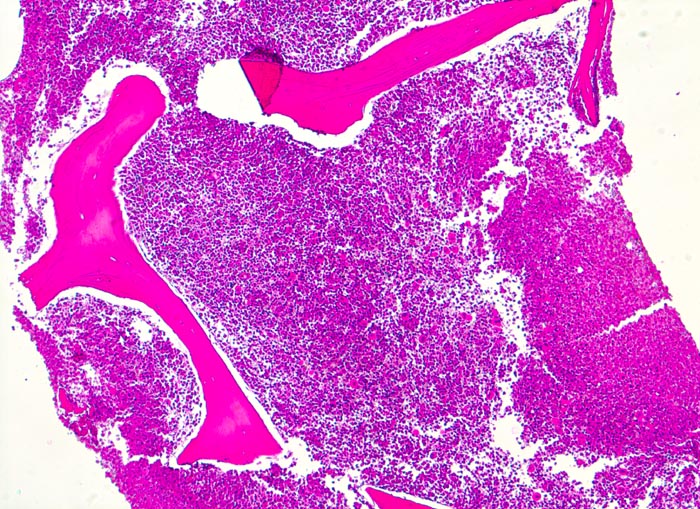

chronische myeloische Leukämie (CML)

Knochenmark, Beckenkamm

Massive Hyperzellularität von 100% (sogenanntes packed marrow). Vollständige Verdrängung von blutbildendem Mark und Fettmark durch Infiltration der chronisch myeloischen Leukämie (normalerweise bei 60jährigem Patienten noch ca. 40% blutbildendes Knochenmark! und 60% Fettmark)

Müdigkeit und Gewichtsverlust. Ausgeprägte Leukozytose, Basophilie und leichte Anämie. Palpable Milz.

Histologie

50